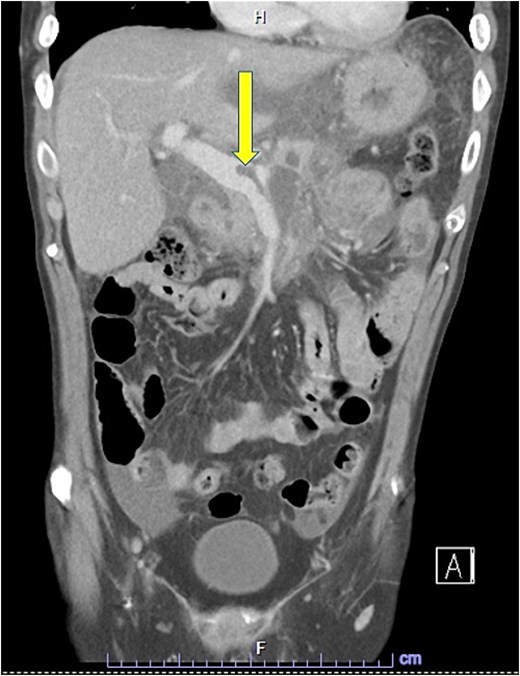

Despite the absence of abdominal symptoms, a computed tomography of the abdomen and pelvis (CTAP) was performed due to markedly elevated lipase levels. The CTAP (Figs 3–5) revealed evidence of acute pancreatitis (Fig. 5, arrow), with a complex peripancreatic fluid collection (Fig. 3, arrow). Additionally, a focal thrombus was observed within the portal venous confluence (Fig. 4, arrow). Further ultrasound of the gallbladder was negative for gallstones (Fig. 6), ruling out gallstone-induced pancreatitis.

CTAP coronal view; complex peripancreatic fluid collection (arrow) with extension behind the splenic vein to lie adjacent to the pancreatic neck and uncinate process.

CTAP coronal view; focal thrombus within the portal venous confluence (arrow).